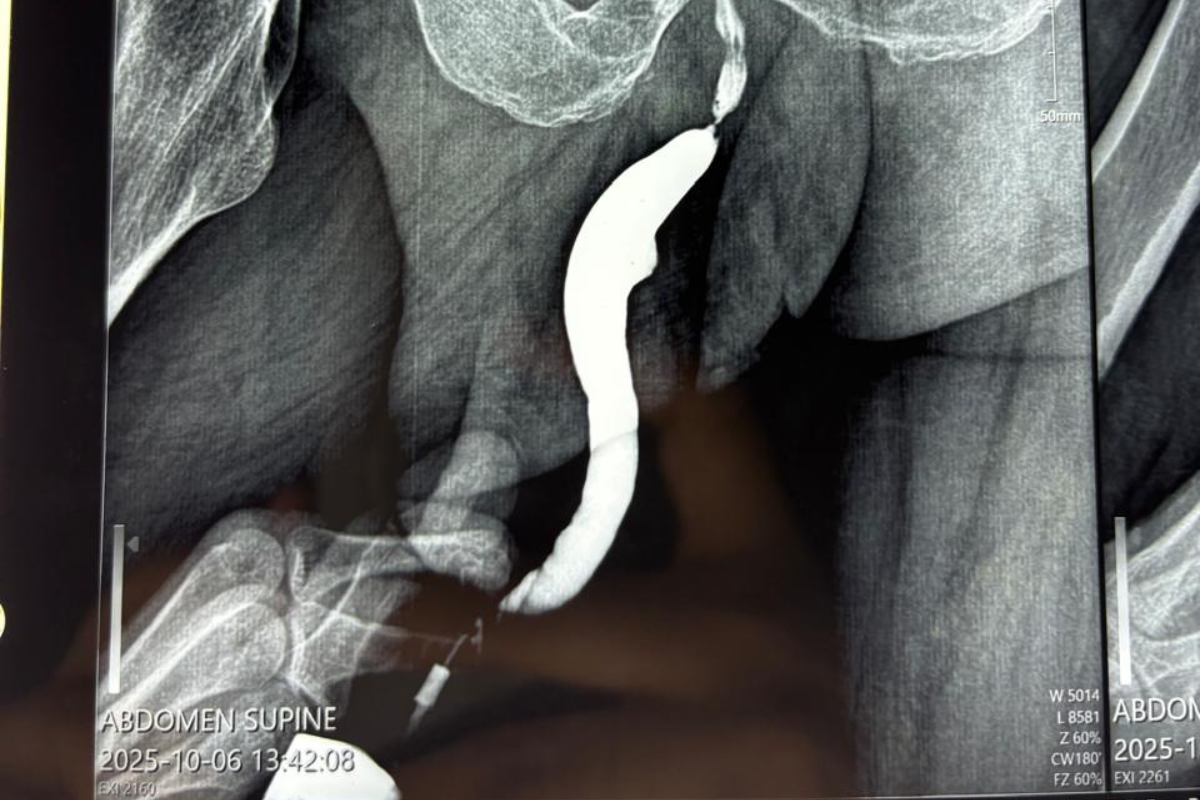

Latest Case Studies

Discover real patient experiences and outcomes in urology. Our case studies highlight advanced treatments, minimally invasive procedures, and successful interventions, reflecting our commitment to expert care and better health.